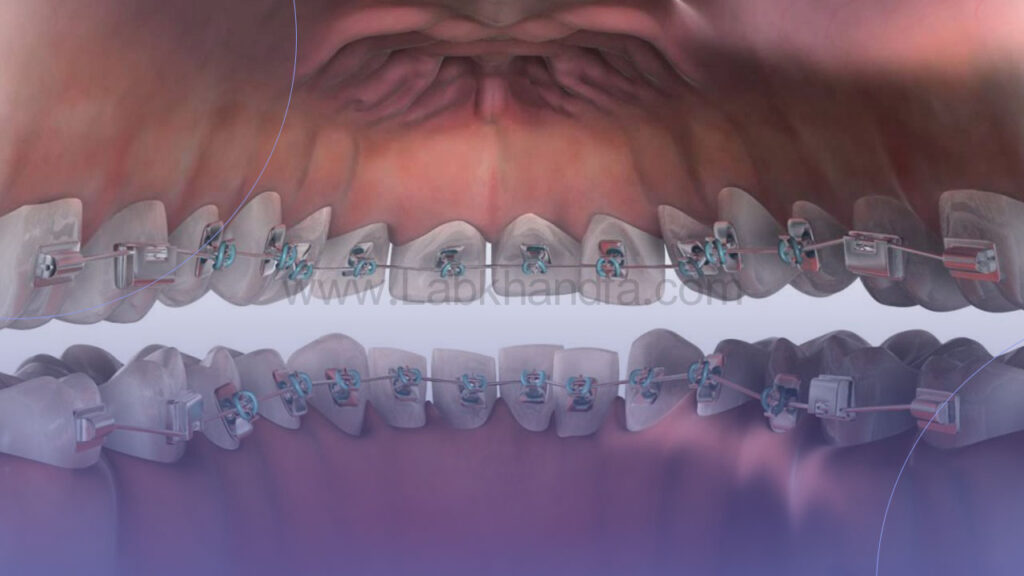

ارتودنسی ثابت

در روش ارتودنسی ثابت از براکت و سیم برای حرکت دادن دندان ها استفاده می شود. کنترل حرکات دندان در این روش بسیار دقیق است و برای ناهنجاری های شدید بهترین گزینه محسوب می شود.